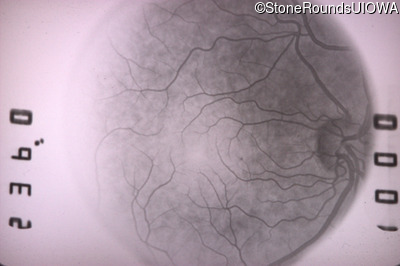

Fluorescein Angiography - Right - 20/25 +2 sc

Exemplar